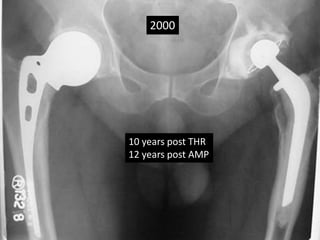

• 36 yrs Male

• AMP done 1988 rt side at the age of 36 yrs

• THR cemented done on left 1990 at the age of 38.

• Revision THR for shattered femur 2007

• Sciatic palsy

• Removal of Memmen plate and wires April 2009.

• Removal of THR Sept 2009.

• Metal fatigue 2012

• Last follow up Nov 2014.

2000

10 years post THR

12 years post AMP